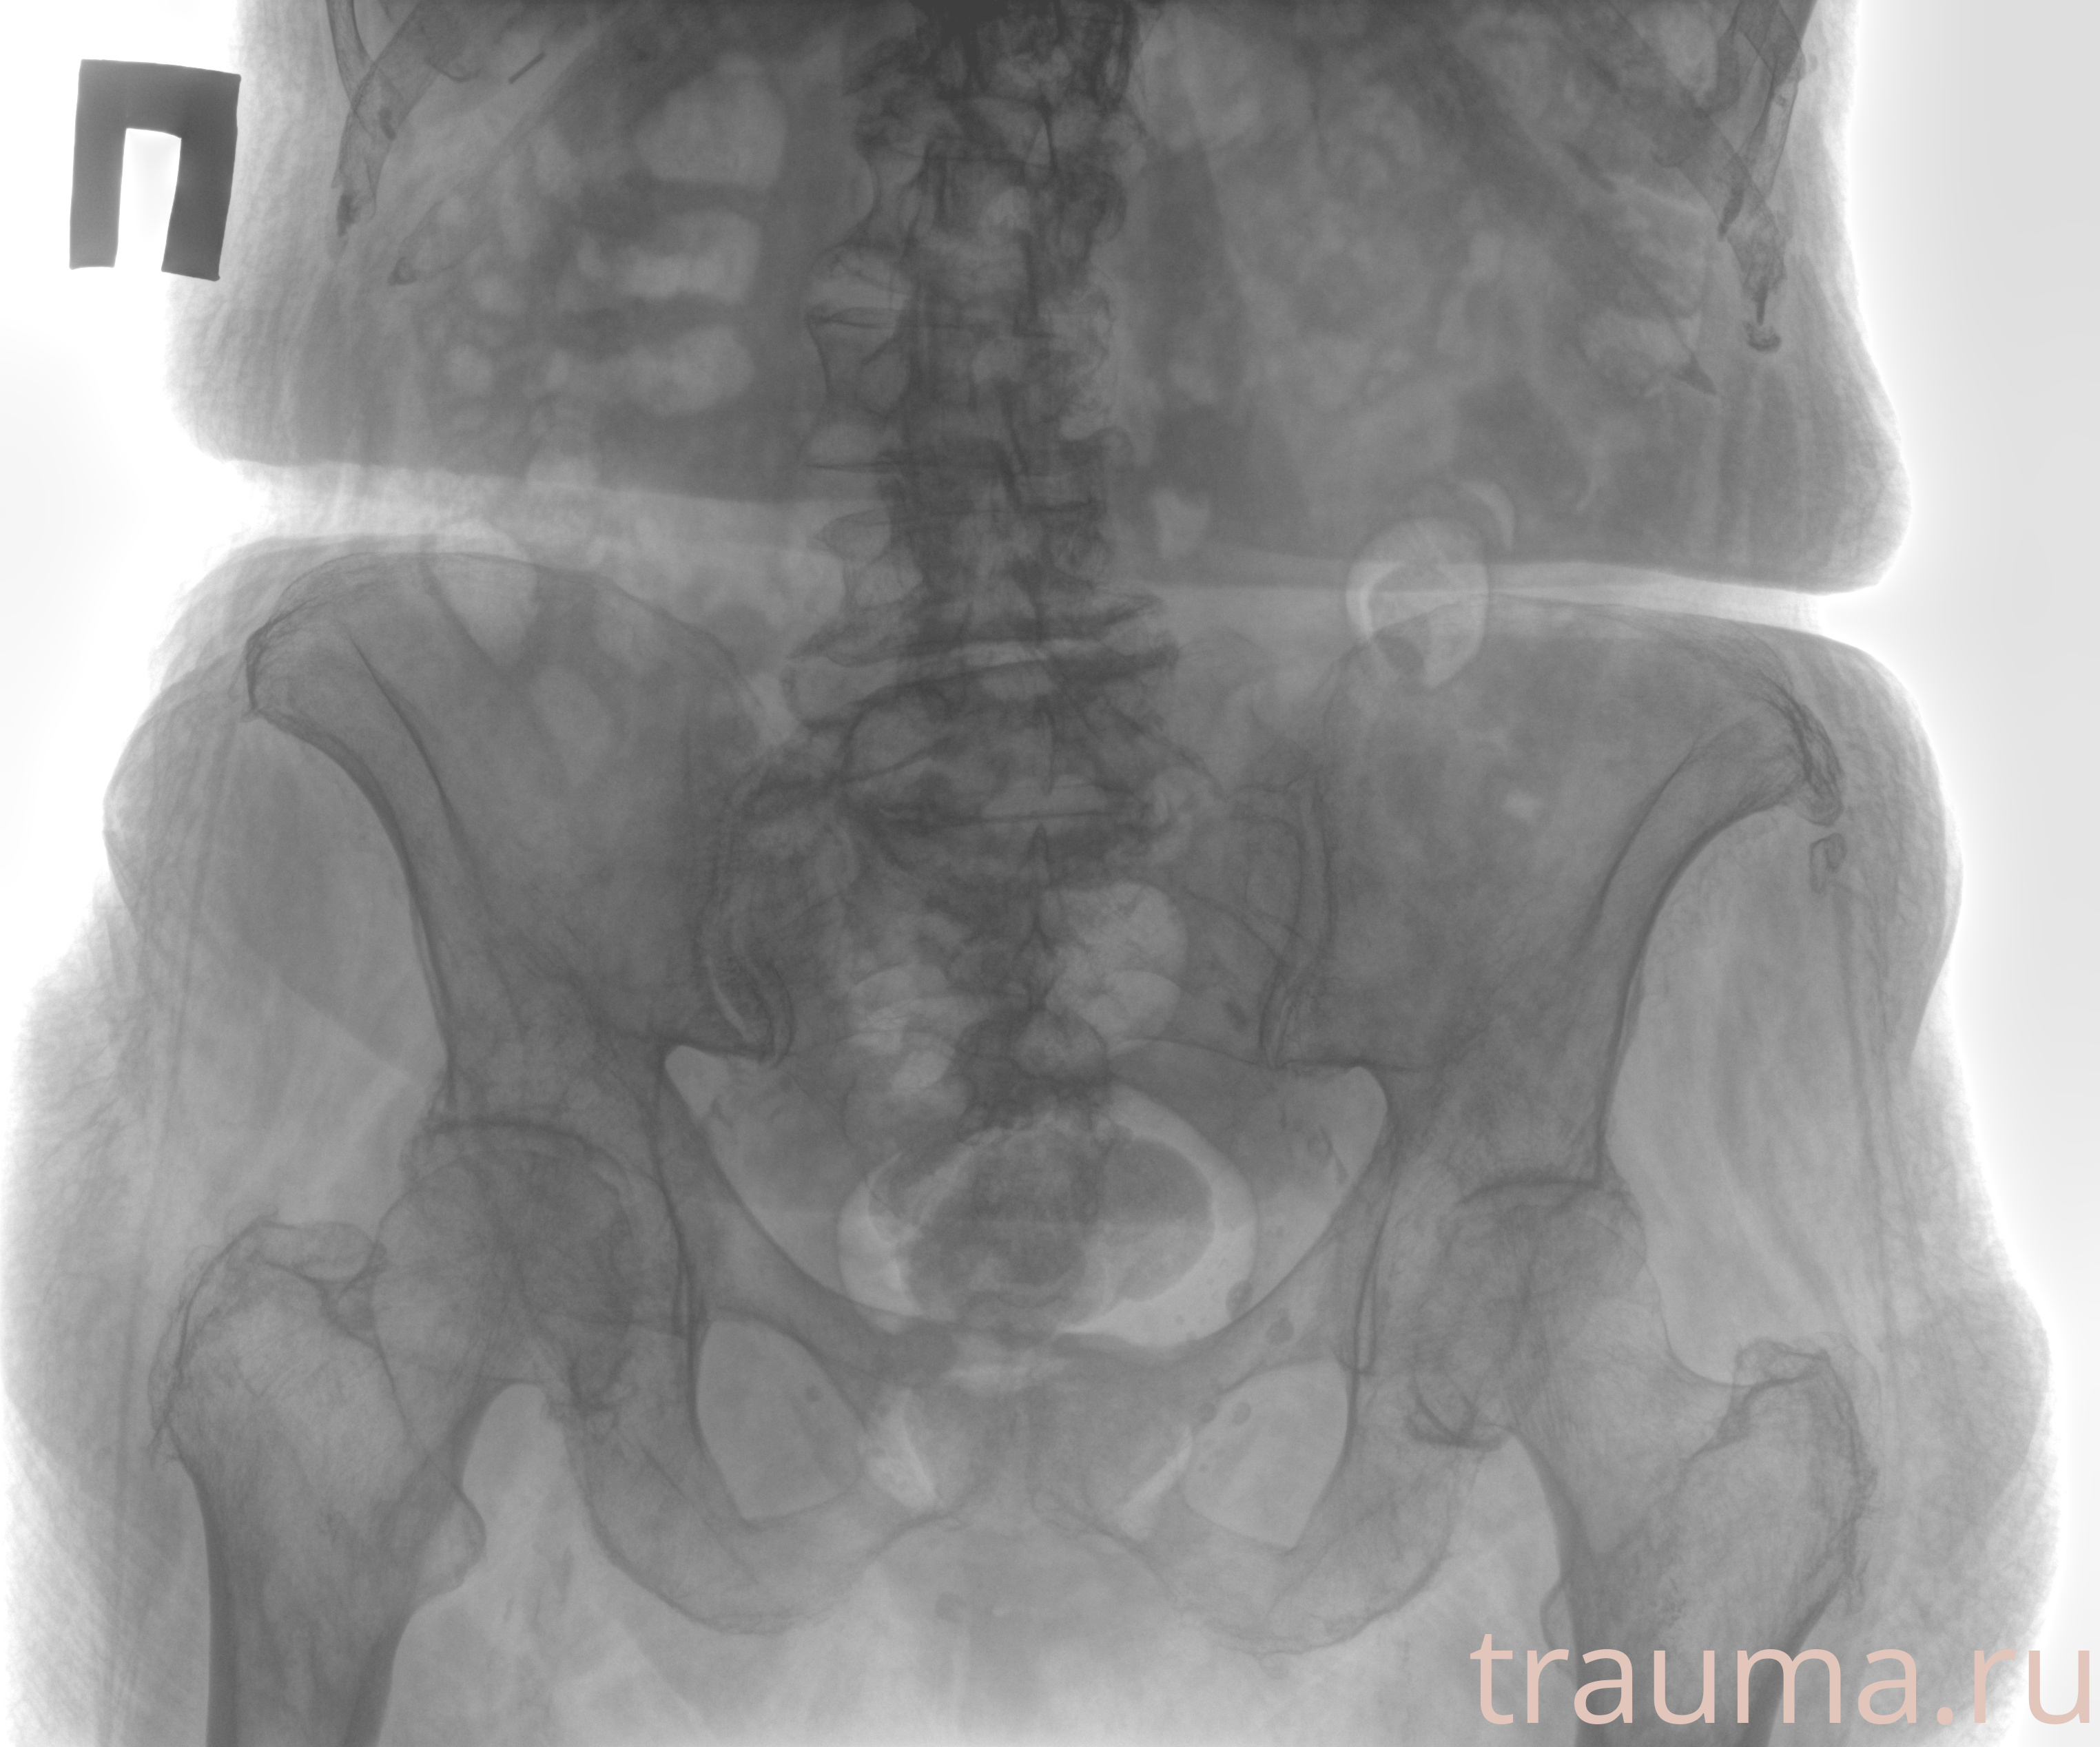

Рентгенограммы

Рентген на дому: по вашему адресу приезжает врач-рентгенолог, травматолог-ортопед с мобильным рентгеновским аппаратом, проводит диагностику травмы или заболевания, делает необходимые рентгенограммы, дает рекомендации по дальнейшему лечению. Получить качественные снимки в домашних условиях возможно благодаря уникальной методике, разработанной МосРентген Центром для института  Склифосовского

при переломе шейки бедра и пневмонии от компании МосРентген Центр - партнера Института имени Склифосовского